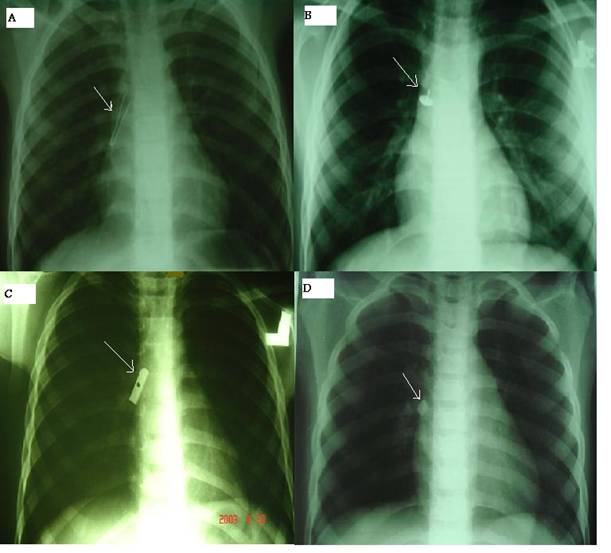

From www.medsci.org

From radiologykey.com